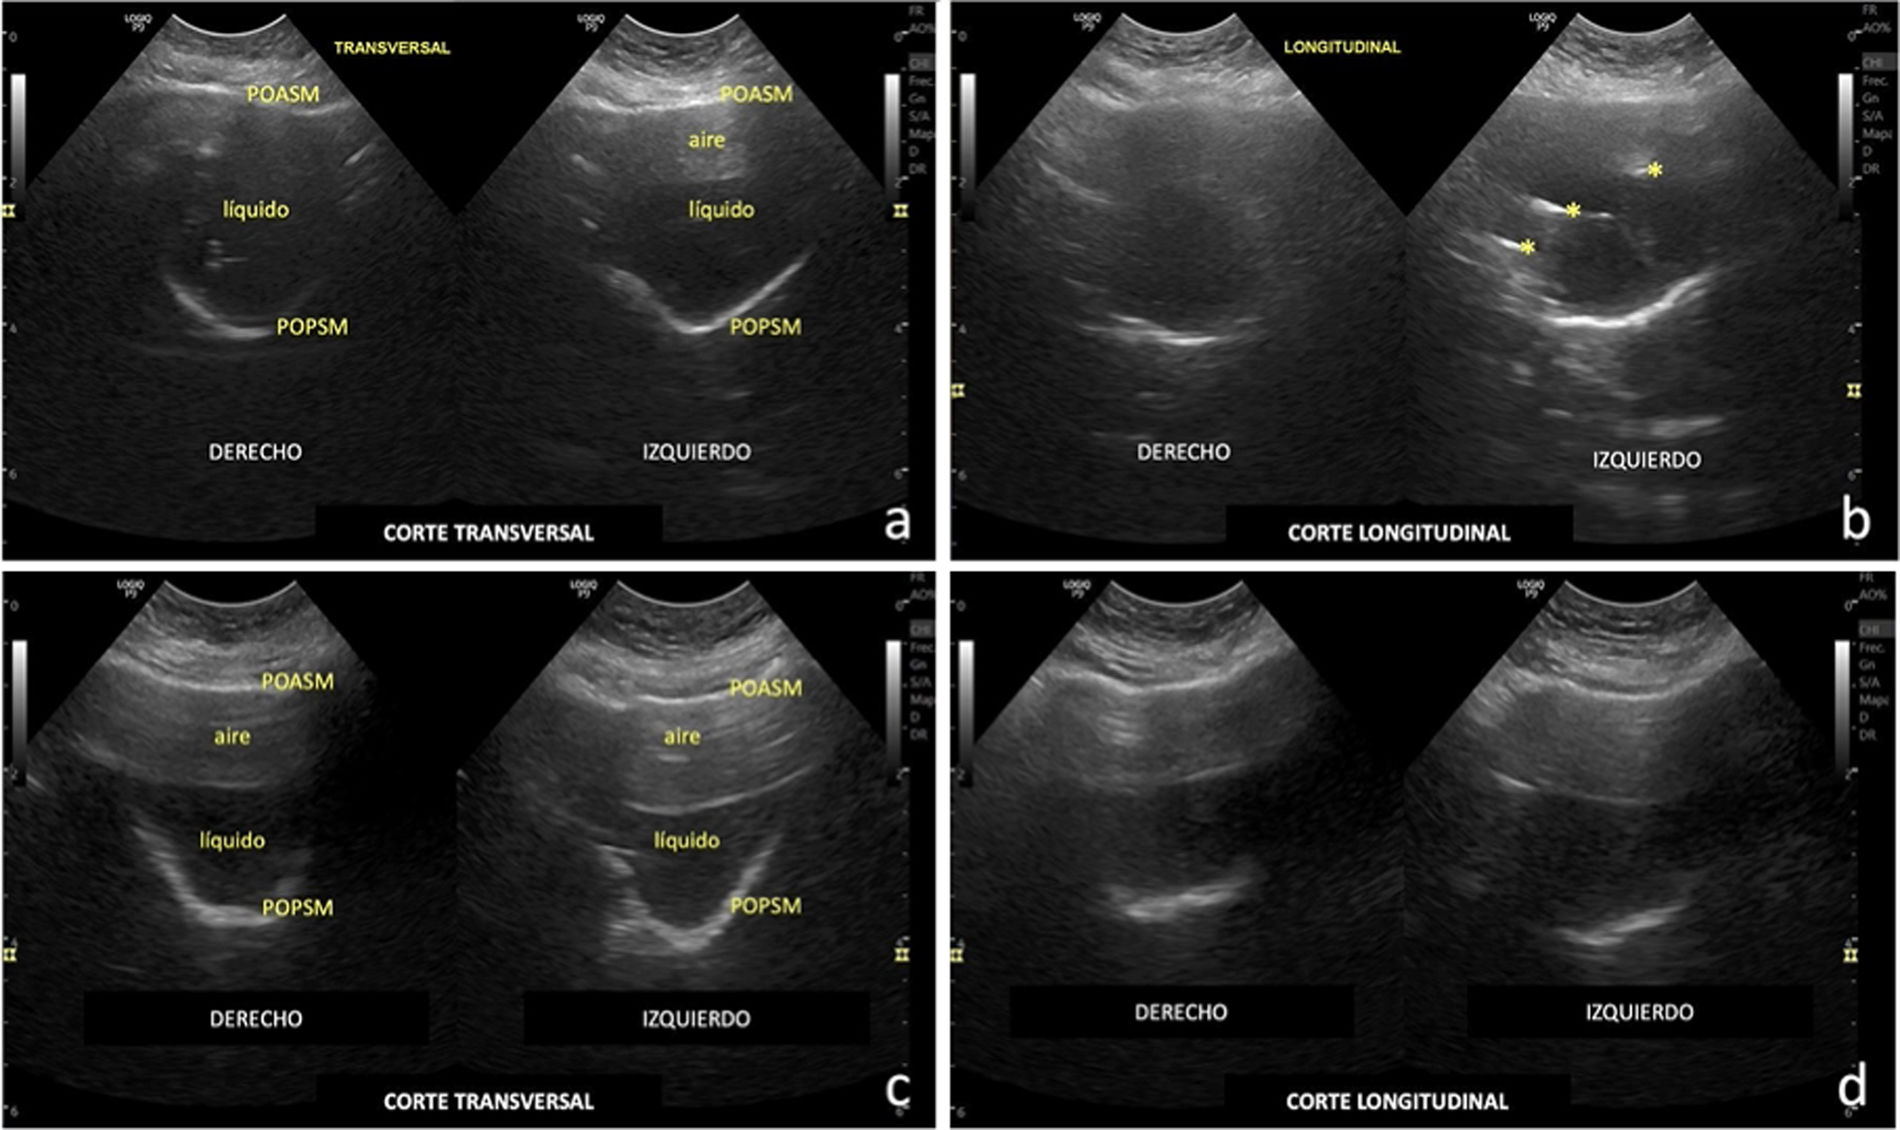

a) Izquierda: corte transversal en modo B, de una paciente adolescente, con semiología clínica de sinusitis aguda, con sonda microconvex (4-10MHz) colocada horizontalmente debajo de la órbita a nivel de la pared anterior del seno maxilar derecho. Se visualiza la pared ósea anterior del seno maxilar (POASM); el seno ocupado (líquido); y la POPSM, que confirman el diagnóstico clínico. Derecha: corte igual que el anterior en la zona contralateral, cuya parte superior del seno se encuentra parcialmente ocupada por aire. b) Cortes longitudinales, que representan planos parasagitales de los senos maxilares de la misma paciente, en el mismo lugar y con la misma sonda, colocada verticalmente, con hallazgos similares. (*) aire en el interior del contenido liquido del seno maxilar izquierdo. Véase la morfología en «V» o «U» de la POPSM en cortes transversales; y la morfología lineal, no paralela a la POASM, en cortes longitudinales. c y d). Imágenes similares a las previas, donde ambos senos maxilares están ocupados por aire (mitad superior) y líquido (mitad inferior) en una paciente de 4 años de edad con semiología clínica de sinusitis subaguda.

En la figura 2 (a y b) se visualizan los senos maxilares ocupados por líquido en una paciente con semiología clínica de sinusitis aguda. En la figura 2 (c y d) se ponen de manifiesto lo senos maxilares ocupados parcialmente por aire (mitad superior) y líquido (mitad inferior) en una paciente con síntomas de sinusitis subaguda. Este hallazgo es especialmente relevante, ya que previamente se consideraba que la presencia de aire impedía la visualización de estructuras posteriores. Sin embargo, en este caso, la presencia de aire no impidió identificar líquido en las zonas declives del seno, incluso en pacientes con clínica menos específica.